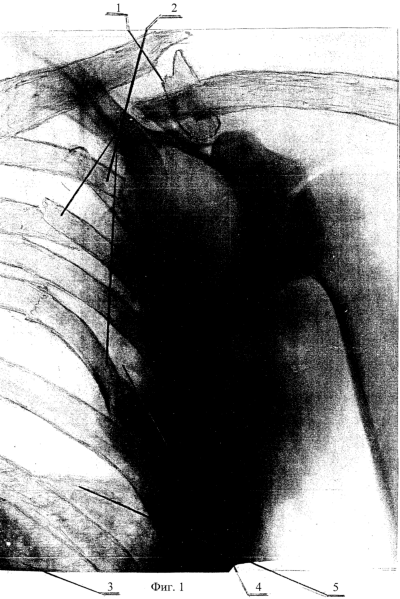

На фиг.1 приведен фотоснимок политравмы: оскольчатый перелом ключицы 1, ребер 2, с выраженным смещением отломков; повреждение легкого 3; гемоторакс 4; диафрагма 5 (история болезни №1327, 2002, Б.А., 36 лет.).